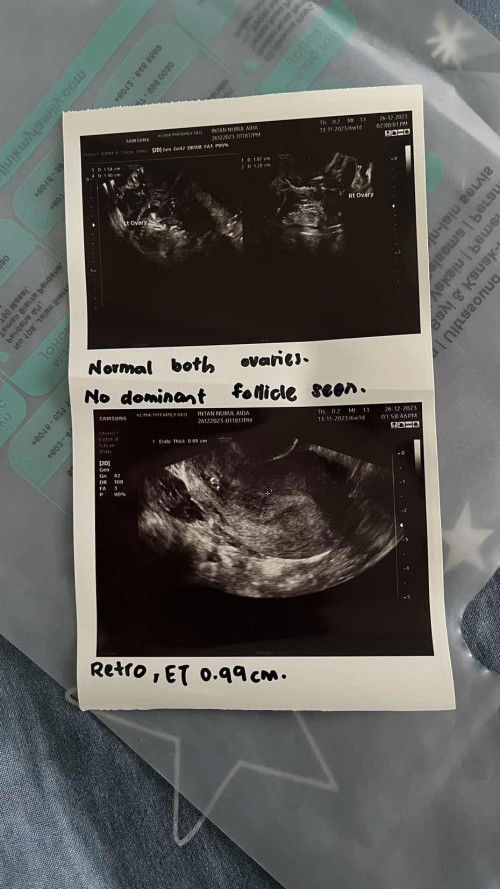

Btw, saya baru 6 bulan kawin dan period saya teratur je tiap2 bulan, cuma bulan ni agak pelik sikit. Bulan lepas saya start period 13/11 last period 19/11 jadi minggu lepas saya pergi scan di klinik, doktor cakap dinding rahim tebal dan proses penempelan berlaku, doktor ambil ujian air kencing pun positive pregnant. And hari ni 26/12 pagi tadi keluar spotting sikit dan saya tak tahu samada tu berlaku darah awal kehamilan ataupun period. Kemudian saya pakai pad tengok macam keluar darah macam period tapi saya tak pasti. Lepas tu tak sedap hati saya terus pergi check di klinik berdekatan. Buat scan kali kedua tapi ni scan dekat klinik lain lah, bukan klinik yg minggu lepas scan tu. Kali ni jawapan doktor agak berbeza, doktor ambil ujian air kencing tetiba negatif dan scan tvs hanya cuma dinding rahim tebal. Kemudian saya proceed last step untuk ambil ujian darah beta hcg untuk mengesan samada saya betul-betul pregnant ataupun tidak. Result dapat tahu esok. Saya ingin menanyakan pernahkan korang alami situasi macam saya? Boleh berkongsi pengalaman sebab saya first time alami situasi ni.